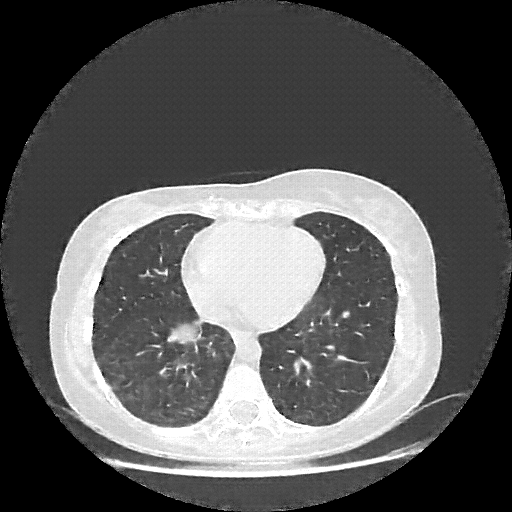

Original VENOUS CT scan

Full window (WL 1023.5, WW 4095 β†’ Low βˆ’1024, High +3071)

Lung window (WL -600, WW 1500 β†’ Low βˆ’1350, High +150)

Mediastinum window (WL 40, WW 400 β†’ Low βˆ’160, High +240)